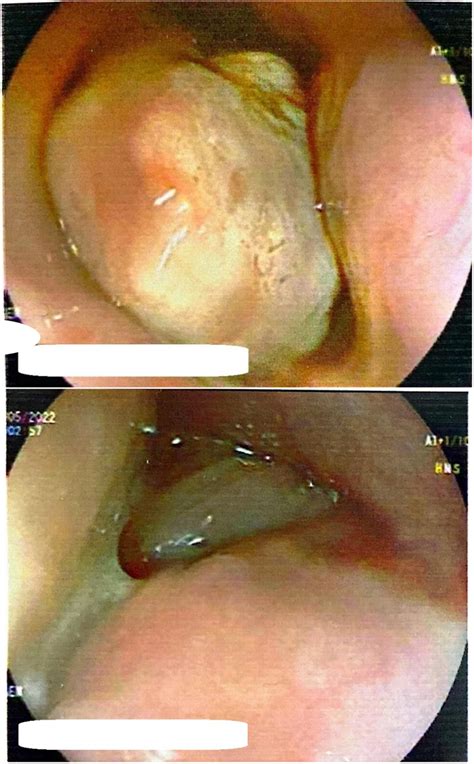

• Fibrovascular Polyps: These are rare, benign lesions that consist of fibrous, adipose, and vascular tissue. They can sometimes grow quite large and cause obstructive symptoms.

• Squamous Papillomas: These are wart-like growths that are often associated with the human papillomavirus (HPV) or chronic mechanical irritation.

• Endoscopic Polypectomy: This is a minimally invasive procedure where the doctor removes the polyp using a wire snare passed through the endoscope.

• Endoscopic Mucosal Resection (EMR): Used for larger or flatter polyps, this involves lifting the lesion and removing it systematically.

• Surgical Excision: In rare cases where the polyp is exceptionally large, pedunculated (attached by a stalk), or located in a difficult area, surgical removal may be required.